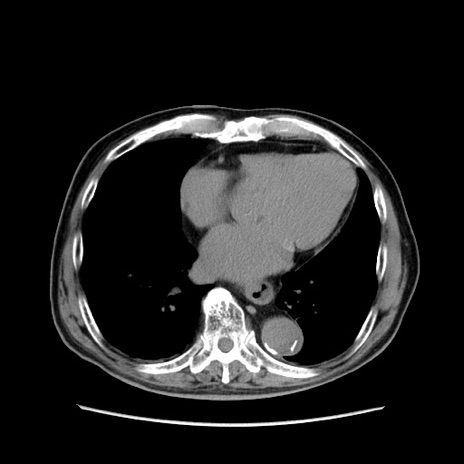

冠状断像